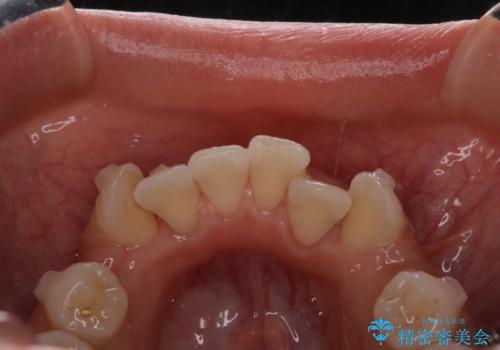

インビザラインで矯正中のコーヒーによる着色をきれいに除去

- インビザライン中に、コーヒーによる着色が気になるとのことでした。PMTC60分コースを行いました。

PMTC(保険外治療)は、毎日の歯磨きで落としきれない汚れや、コーヒ、紅茶・タバコのヤニなどの着色も除去します。目には見えない歯と歯の間・歯肉の境目・インビザライン中はアタッチメント周囲などに残っているプラーク(歯垢)もしっかり取り除きます。PMTCでは専門的な機械や材料を使用して、徹底的に汚れを除去するため、虫歯・歯周病・口臭予防などにつながります。

またPMTCを行うことで、ご自身本来の歯の色になり自然な明るさになります。